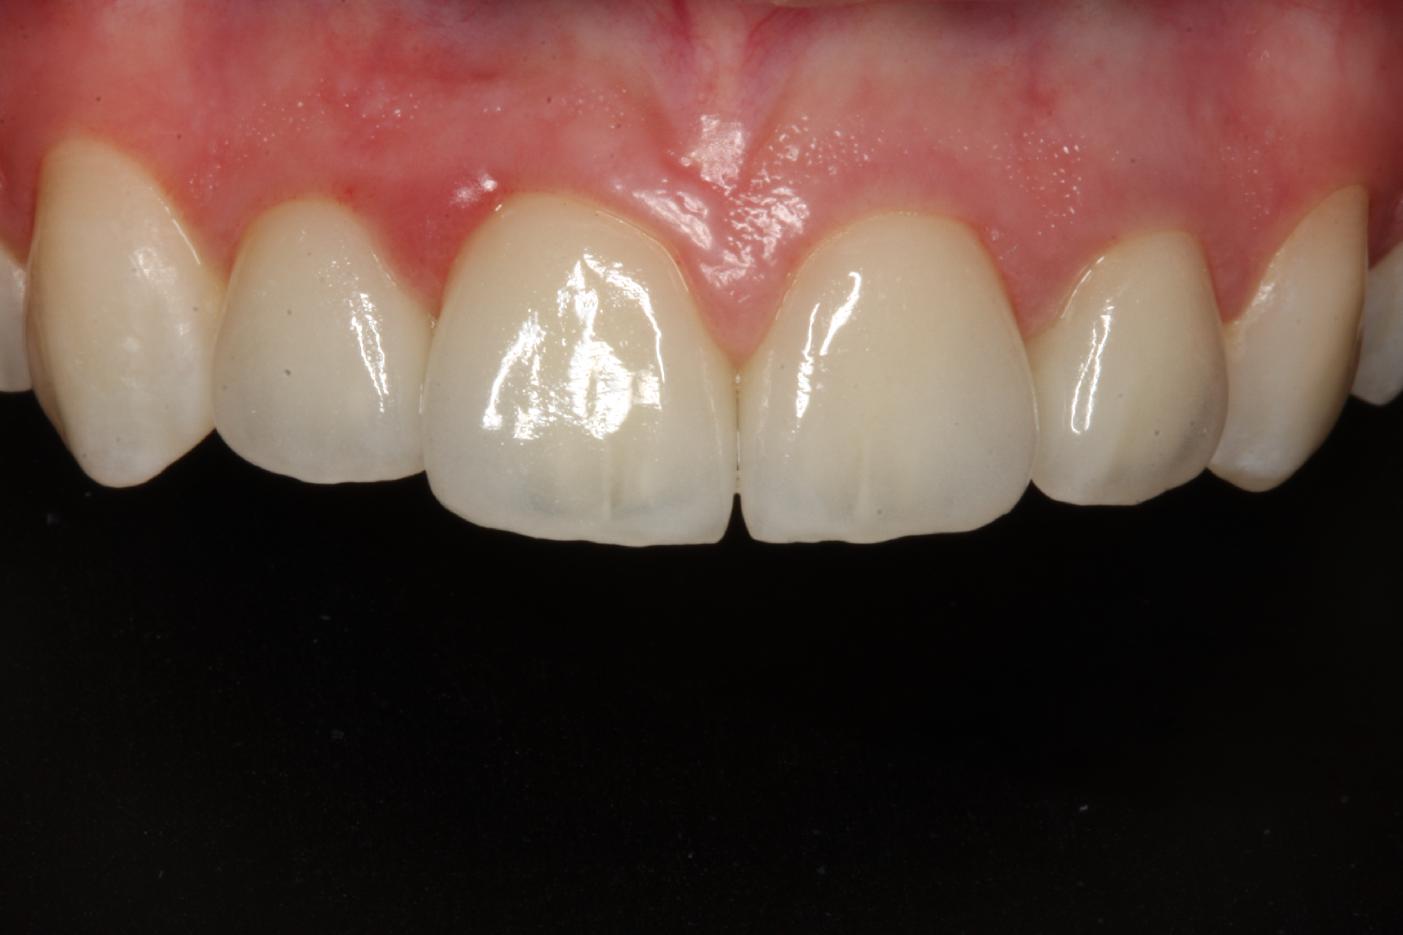

1/12 - Initial clinical situationSoft tissue thickening at immediate implant placement and GBR with mucoderm® and maxgraft® - Dr. A. Puisys

Initial view of the case. Discoloration of 1.1 and mild class I gingival recession

Initial clinical situation with Miller class 1 recession

Initial clinical situation

Initial clinical situation showing strongly compromised tooth 21